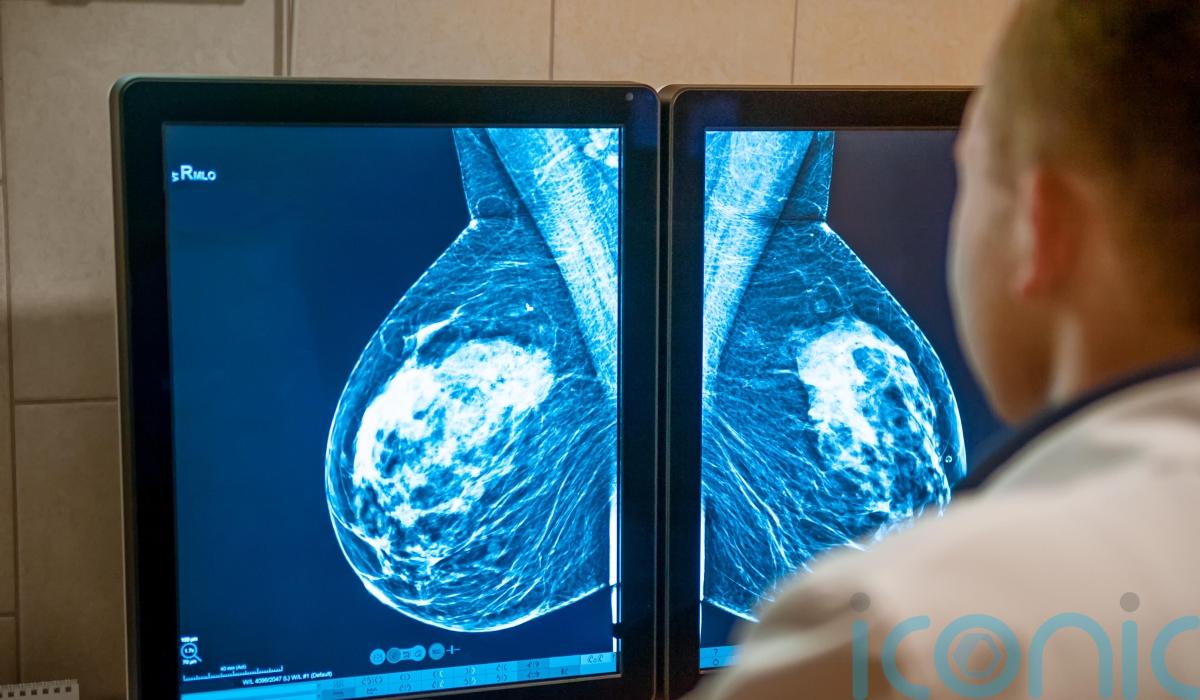

Ms Herbst Taylor said a national screening programme is needed for ovarian cancer, similar to schemes already in place to try to detect cases of breast and cervical cancer.

She added: “We have national screening programmes for breast and cervical cancer, we do not have one for ovarian cancer.